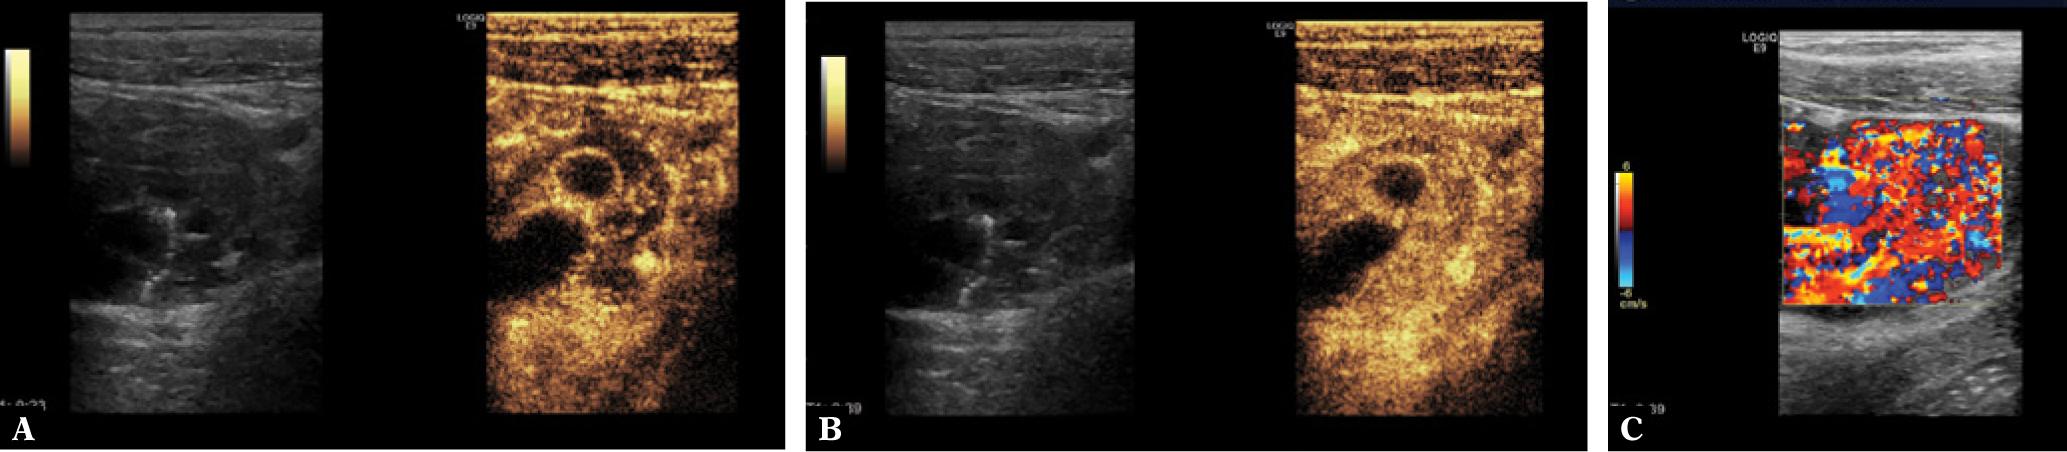

The following figures show transmural endometriosis infiltrating the sigmoid colon and present endoscopy, ultrasound, CEUS and endoscopic ultrasound findings. A 24-year old woman complained of recurrent lower abdominal pain for 6 months. She was referred for colonoscopy. There was no palpable mass on digital rectal examination. Blood chemistry, full blood count, coagulation profile, alfa-fetoprotein and carcinoembryonic antigen were within normal limits. Colonoscopy revealed a semi-circular polypoid lesion in the sigmoid colon suggesting malignancy (Fig. 1). The biopsy taken at colonoscopy was diagnostic for endometriosis and surgical treatment was planned. Other imaging modalities were arranged to stage the local disease and to exclude further manifestations. Transabdominal B-mode ultrasound (BMUS) confirmed a 40 mm sized heterogeneous hypoechoic transmural lesion infiltrating the sigmoid colon (Fig. 2). Contrast enhanced ultrasound showed a rapidly and heterogeneously enhancing lesion during the arterial and venous phases (Fig. 3). Contrast enhanced colour Doppler ultrasound confirmed the finding. Endorectal endoscopic ultrasound of the sigmoid colon revealed transmural extension of the mass and confirmed the transcutaneous finding (Fig. 4). The lesion was well vascularized (Fig. 2 and Fig. 4). Magnetic resonance imaging did not add any additional information. Subsequently, the patient underwent laparoscopic sigmoid resection. Pathological examination revealed extragenital endometriosis. Microscopic examination disclosed endometrial stroma and gland islands located between muscular fibres, subserosa and serosa. The postoperative period was uneventful.

Transabdominal B-mode ultrasound (BMUS) confirmed a 40 mm sized heterogeneous hypoechoic and hypervascular lesion infiltrating the sigmoid colon (A–C) using the conventional abdominal probe (A ), high frequency transducer for more details (B) and color Doppler imaging (C)

After administering contrast agents, the lesion showed rapid heterogeneous hyperenhancement during early arterial phase (A) and late phase (B). After CEUS, blood flow signals in the lesion were increased (C)